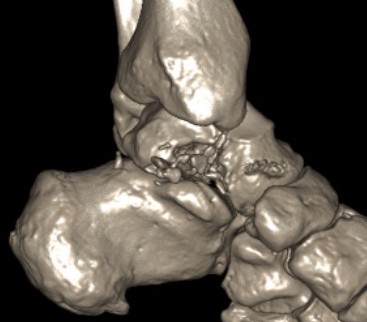

Type III: Talar body dislocated from ankle joint

Type IV: Talar head dislocated from talonavicular joint

Irreducible fractures / Extruded Talus

Anatomical reduction + fixation

1. Remove loose bodies from subtalar joint

2. Reduction - avoid varus and shortening medial neck

- often medial comminution